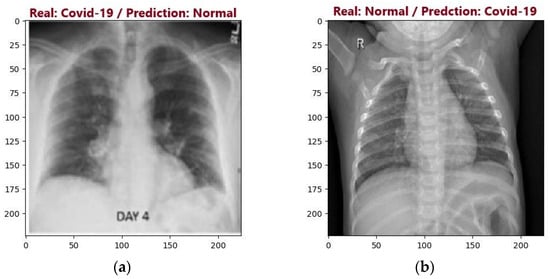

4.2.3. Analysis of Results